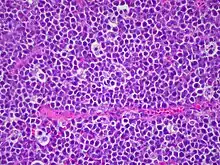

![]() Células típicas del linfoma de Burkitt. | ||

El linfoma de Burkitt bajo el microscopio consiste en población monótona de capas celulares de tamaño medio con una gran actividad proliferativa y apoptótica. La apariencia se asemeja a una noche de estrellas, por razón de las inclusiones esparcidas de los macrófagos que han digerido las partes celulares muertas. Las células del tumor tienen un tamaño muy similar al de los histiocitos o células endoteliales, de modo que no son células muy grandes, sino de mediano tamaño. Las células tumorales tienen una pequeña cantidad de citoplasma que se tiñe basofílica. Los contornos celulares tienen la apariencia de ser cuadriláteras.